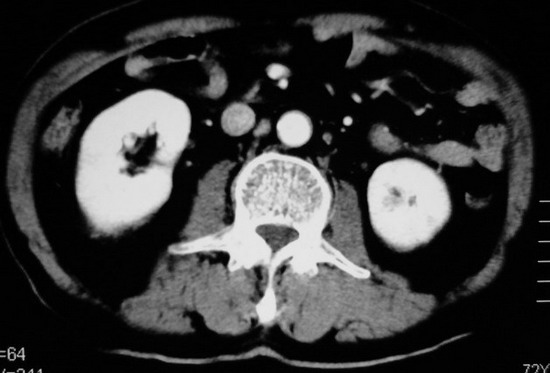

以下是引用杀毒软件在2008-11-17 19:15:00的发言:[br]考虑------右肾癌合并肾静脉---同侧肾上腺受侵可能性大

以下是引用zjzjr在2008-11-17 20:45:00的发言:[br]考虑------右肾癌合并肾静脉---同侧肾上腺受侵可能性大及腹膜后淋巴结转移.